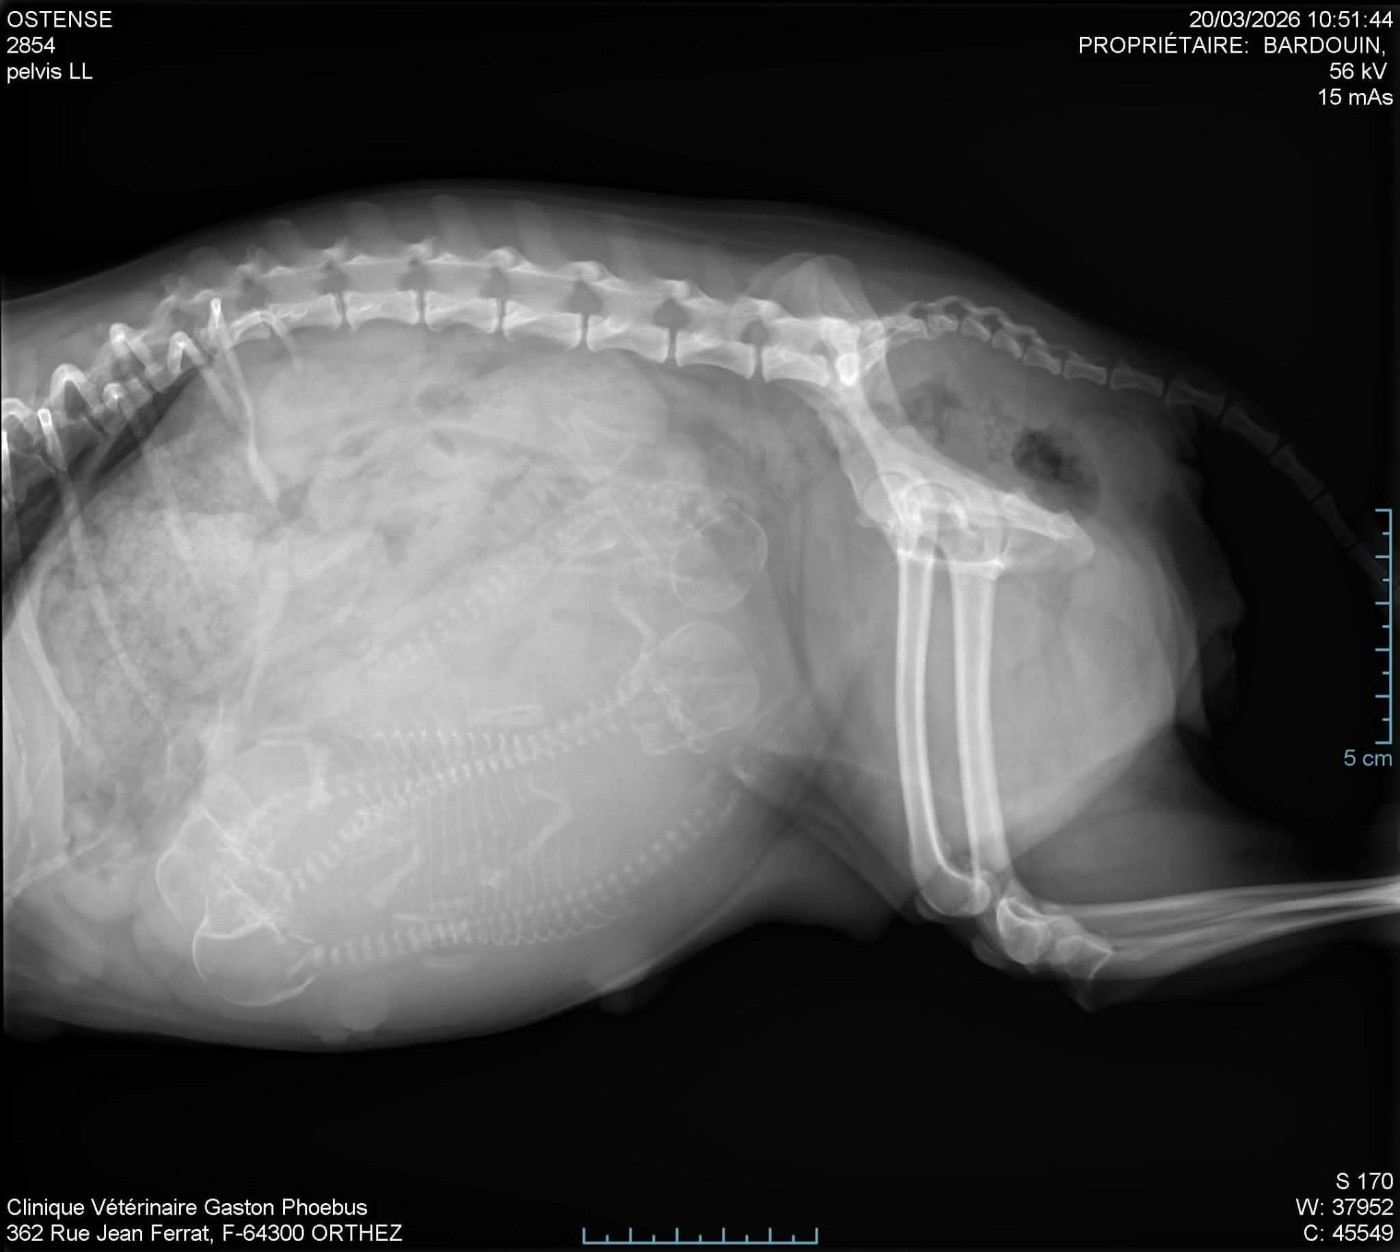

Umenji radio prévue lundi pour le nombre de ses bébés

Umenji naissance de ses bébés

Hostance 💗 bientôt ses bébés 💕4 bébés ☀ ❤ ☀